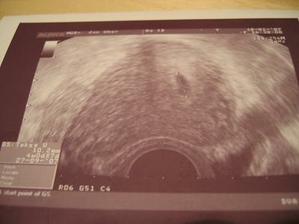

1.3.2007 - miminko se má k světu.....vrtí se, kope nožkama......,ale máme pořád problémy s hematomy. Ach jo........

23.4......19+5 , Máme už skoro 280g, a cítím pohyby. Nejspíš to bude holčička 🙂